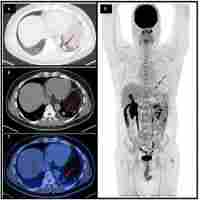

| Description | The role of 18F-FDG PET/CT imaging in patient with malignant PEComa treated with mTOR inhibitor Lu Sun,1 Xiaorong Sun,2 Yuhui Li,3 Ligang Xing4 1School of Medicine and Life Sciences, University of Jinan-Shandong Academy of Medical Sciences, 2PET/CT Center, Department of Radiology, 3Department of Pathology, 4Department of Radiation Oncology, Shandong Cancer Hospital and Institute, Jinan, Shandong, People's Republic of China Malignant perivascular epithelioid cell tumor (malignant PEComa) is a rare disease for which the diagnostic criteria and treatment options have not been established. Since PEComa is associated with upregulation of mammalian target of rapamycin (mTOR) pathway which controls Glut-1 (glucose transporter) function, increased 18F-fluorodeoxyglucose (18F-FDG) uptake may indicate the over activation of mTOR pathway and may guide selectively inhibiting mTOR pathway treatment. We report a malignant PEComa patient who presented for 18F-FDG positron emission tomography/computed tomography (PET/CT) restaging. The tumor had shown significant avidity on PET/CT as well as an evident response to sirolimus (rapamycin, Rapamuneā¢) that supports the utility of mTOR inhibitors as an effective treatment for malignant PEComa. Therefore, 18F-FDG PET/CT is helpful in restaging and guiding treatment for malignant PEComa with mTOR inhibitors. Keywords: malignant perivascular epithelioid cell tumor, PEComa, mTOR inhibitor, FDG, PET/CT |